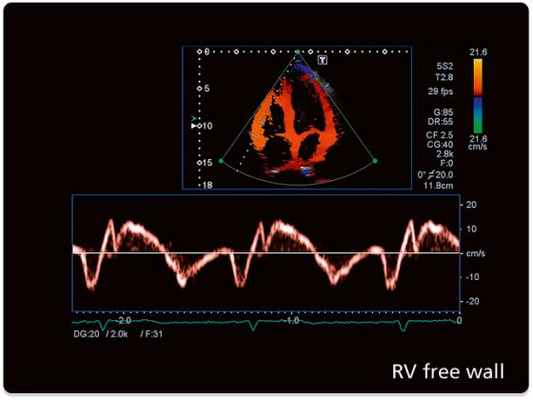

Техническая справка: Эхокардиография с допплерометрией и ЦДК

Эхокардиография с допплерометрией и цветным допплеровским картированием (ЦДК) – это сочетание обычного двумерного ультразвукового сканирования сердца для анализа его анатомии с допплерометрией. Эффектом Допплера называется физическое явление изменения частоты ультразвука при отражении его от движущихся объектов. Допплерометрия позволяет оценить ток крови, его направление, скорость и характер, а в сердце выявить недостаточность и стеноз клапанов, отрывы хорды и т.д. Сочетание обычного двумерного серошкального УЗИ с допплерометрией плюс добавление цветовой кодировки потоков крови (от УЗ-датчика и к нему) – это цветное допплеровское картирование. С его помощью наши специалисты сразу видят патологические забросы крови (из полости левого желудочка во время систолы в левое предсердие при недостаточности митрального клапана).